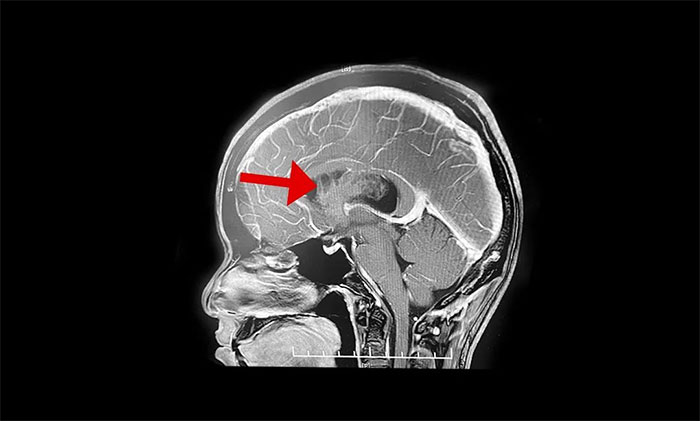

最终被诊断为中枢神经细胞瘤。中枢神经细胞瘤属于比较罕见的脑肿瘤,一般直径超过三公分即为巨大肿瘤,而李威脑室内的肿瘤直径竟达七公分,接近一个拳头大小。幸运的是,顺利手术切除。

上海蓝十字脑科医院神经外科李士其教授介绍,中枢神经细胞瘤(Central neurocytoma,CN)是少见的神经系统肿瘤,1982年由Hansson首次报道并命名,2016年WHO神经系统肿瘤组织学分类将其归类为神经元和混合型神经元胶质瘤(WHOⅡ级)。中枢神经细胞瘤仅占颅内肿瘤的0.25%~0.50%,好发于20~40岁青年人,无性别差异。病史一般较长,可达数十年之久,好发于侧脑室透明隔,当病变累及Monro孔时,阻塞脑脊液循环,引起头痛、头晕、恶性、呕吐以及不同程度视力改变等非特异性颅内高压症状。

李士其教授介绍,该肿瘤一般生长于侧脑室或三脑室,由于生长的位置处于脑室内,有较大空隙代偿,疾病初期症状并不典型,当出现如头痛、呕吐等临床症状时,瘤体已经比较大。在治疗上首先建议进行手术切除,解除肿瘤占位效应,通畅脑脊液通路,缓解脑积水,解除颅内高压。李士其教授指出,中枢神经细胞瘤一般为偏良性肿瘤,若能手术全切肿瘤,或者大部分切除后辅助放疗可以长期生存。所以,手术这一步非常关键。

但由于肿瘤较大、血供丰富,且与脑室壁黏连明显,致使肿瘤分离及切除异常困难。而且脑室内血管及神经组织结构复杂、功能重要,如何在切除肿瘤的同时尽可能保护脑功能是手术的最大难点。